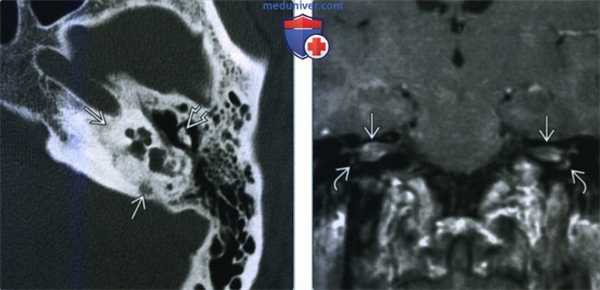

(Слева) При аксиальной КТ височной кости определяются похожие, но менее тяжелые изменения слуховой капсулы и слуховых косточек, обусловленные отосифилисом. Другие костные структуры среднего уха и сосцевидный отросток не изменены. Постлучевые изменения височной кости на КТ могут имитировать отосифилис.

(Справа) При корональной МРТ Т1 С+ определяется патологическое лептоменингеальное контрастирование во внутренних слуховых каналах и перепончатом лабиринте. Это лабиринтит-менингит, обусловленный отосифилисом.